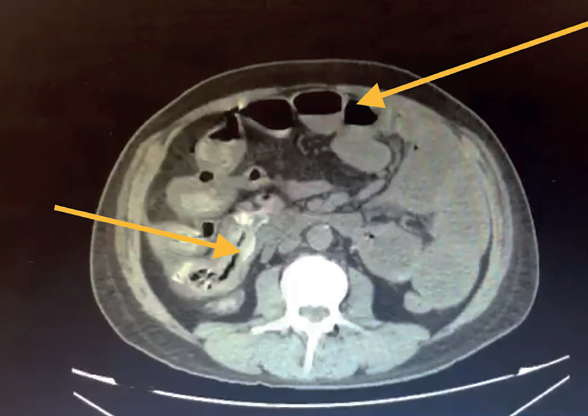

Se le realizó tomografía axial computada el 10-05-2021, donde se identificó: asas de intestino delgado de contenido heterogéneo a expensas de gas y líquido, múltiples imágenes amorfas hiperdensas con atenuaciones que van de 252 HU a 820 HU, en duodeno y yeyuno, así como estriación de su grasa, hacia íleon presenta dimensiones y morfología conservados. Colon con material de residuo en su interior, así como material hiperdenso y disminución de su calibre desde su porción descendente. A nivel de grasa mesentérica adyacente a región ileocólica se observa estriación así como congestión de vasos a ese nivel e imágenes saculares dependientes de pared. Escaso aire libre perihepático, perivesicular y subdiafragmático. Conclusión ileítis con datos de íleo. Neumoperitoneo duodeno y yeyuno de contenido heterogéneo de etiología a determinar. Estriación de la grasa y congestión de vasos mesentéricos (figuras 2 y 3).

Figura 2 Asas de intestino delgado de contenido heterogéneo a expensas de gas y líquido, con niveles hidroaéreos, múltiples imágenes amorfas hiperdensas con atenuaciones que van de 252 HU a 820 HU, en duodeno y yeyuno.